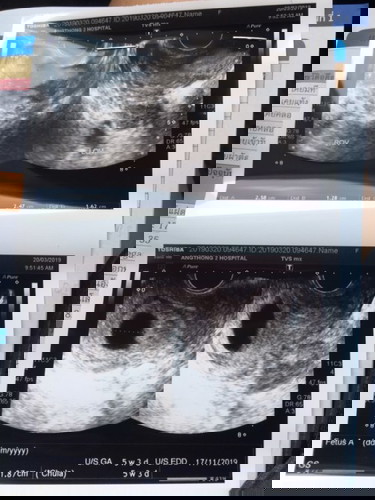

ประจำเดือนวันแรกครั้งสุดท้าย 14 ม.ค. นับได้ 9สัปดาห์2วัน แต่วันนี้ไปซาวเจอแค่ถุงตั้งครรภ์ ในใบซาว 5 สัปดาห์3วัน แบบนี้ไข่ตกช้าหรือว่าท้องลมคะ อยากทราบว่าครั้งต่อไปจะเจอตัวอ่อนเด็กไหมมม ใครเคยมีประสบการณ์ช่วยแนะนำทีค่า คุนแม่จิตตก ? ขอบคุณมากค่ะ